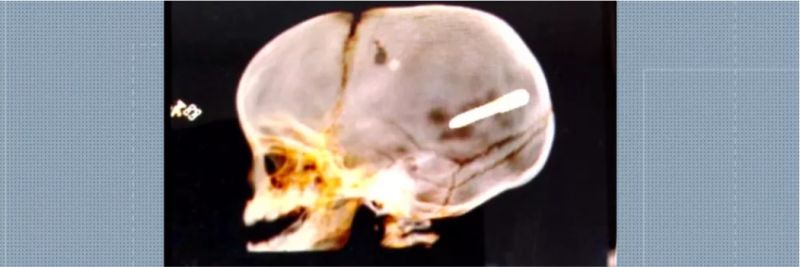

Um funcionário de uma obra próxima ao local onde um bebê morreu após ser atingido por um prego apresentou na 35ª DP (Campo Grande) a pistola usada na construção e que pode ter disparado a peça.

Segundo o delegado Luis Mauricio Armond, ainda será feita uma perícia, mas tudo aponta para uma "fatalidade" no caso. Na manhã desta quinta-feira (1), o corpo do bebê Wallace Martim dos Santos, de apenas 10 meses, ainda estava no Instituto Médico Legal, aguardando liberação.

A família contou para a polícia que o menino estava no colo da mãe, dentro do carro, quando eles ouviram um forte estampido e perceberam que o bebê tinha sido atingido pelo prego. O objeto, segundo os pais, parecia um dardo que é usado para colocar gesso em obras.